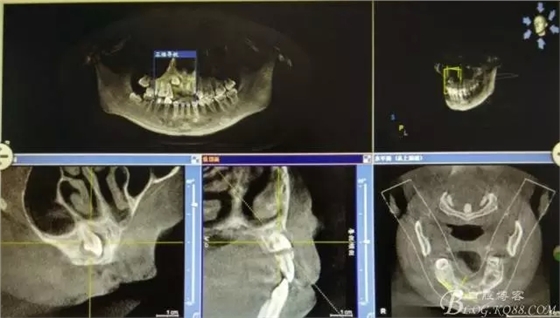

病例資料: 患者、柴xx、女、16歲。??茩z查及病歷如下圖: 患者同意我院正畸科建議,遂轉(zhuǎn)診倒外科。術(shù)前簽知情同意書。 治療過程: 圖1.術(shù)前的CBCT檢查:13阻生,疑為含牙囊腫。縱剖面顯示12牙根吸收至根尖1/3。 圖2.局部麻醉下 。行唇側(cè)弧形切口,12松動不到1°。 圖3.翻瓣、暴露骨面。 圖4.去骨、 暴露13牙冠 圖5.去骨、逐漸顯露13。 圖7.拔除13. 圖8.摘除囊壁 圖9.必須完整剝離囊壁。 圖10.摘除囊壁后形成的骨腔 圖11.超聲骨刀12根尖倒預(yù)備 圖13. 消毒棉球骨腔內(nèi)隔濕血液,紙尖干燥倒預(yù)備好的根管 圖14. 紙尖無血即可 圖15。MTA倒充填 圖16.骨腔填塞膠原蛋白海綿 圖17.拔除的13及摘除的囊壁 圖18.縫合 圖19.術(shù)后x線根尖片影像:MTA封閉根尖